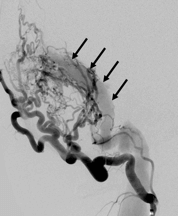

Durale AV Fisteln sind Kurzschlußverbindungen zwischen einer Arterie und einer Vene auf Ebene der harten Hirnhaut (Dura). Sie können nach einer Schädelverletzung oder eine Thrombose eines venösen Blutleiter im Gehirn entstehen, aber oft kann die Ursache nicht sicher bestimmt werden. Bei AV-Fisteln strömt arterielles Blut ohne das zwischengeschaltete Kapillarbett direkt in venöse Gefäße. Aufgrund des höheren Drucks kommt es zu einer Aufweitung der Venen, wodurch das Risiko einer Hirnblutung zunimmt.

Ist eine AV-Fistel durch MRT und eine diagnostische Angiographie sicher nachgewiesen, gibt es in Abhängigkeit von der Lage und Ausdehnung der Fistel verschiedene endovaskuläre Behandlungsoptionen. Heute wird in den meisten Fällen versucht, die AV-Fistel unter Erhalt der venösen Blutleiter zu veröden (Embolisation). Hierfür wird ein sehr dünner Katheter („Mikrokatheter“) über die Leiste bis in die Fistelgefäße geführt. Dies geschieht unter Vollnarkose. Über den Katheter wird ein Embolisat in die Fistelgefäße gespritzt, um diese zu verkleben bzw. zu verstopfen. Für die Embolisation kommen verschiedene Materialien zur Anwendung, überlicherweise werden heute Flüssigembolisate verwendet. Bei ausgedehnten Fisteln kann ein Ballonkatheter über die Leistenvene in den beteiligten venösen Blutleiter in das Gehirn eingelegt werden, um die Vene während der Embolisation vor einer Verstopfung durch das Flüssigembolisat zu schützen. Je nach Größe und Lokalisation der Fistel sind mitunter mehrere Behandlungen notwendig.